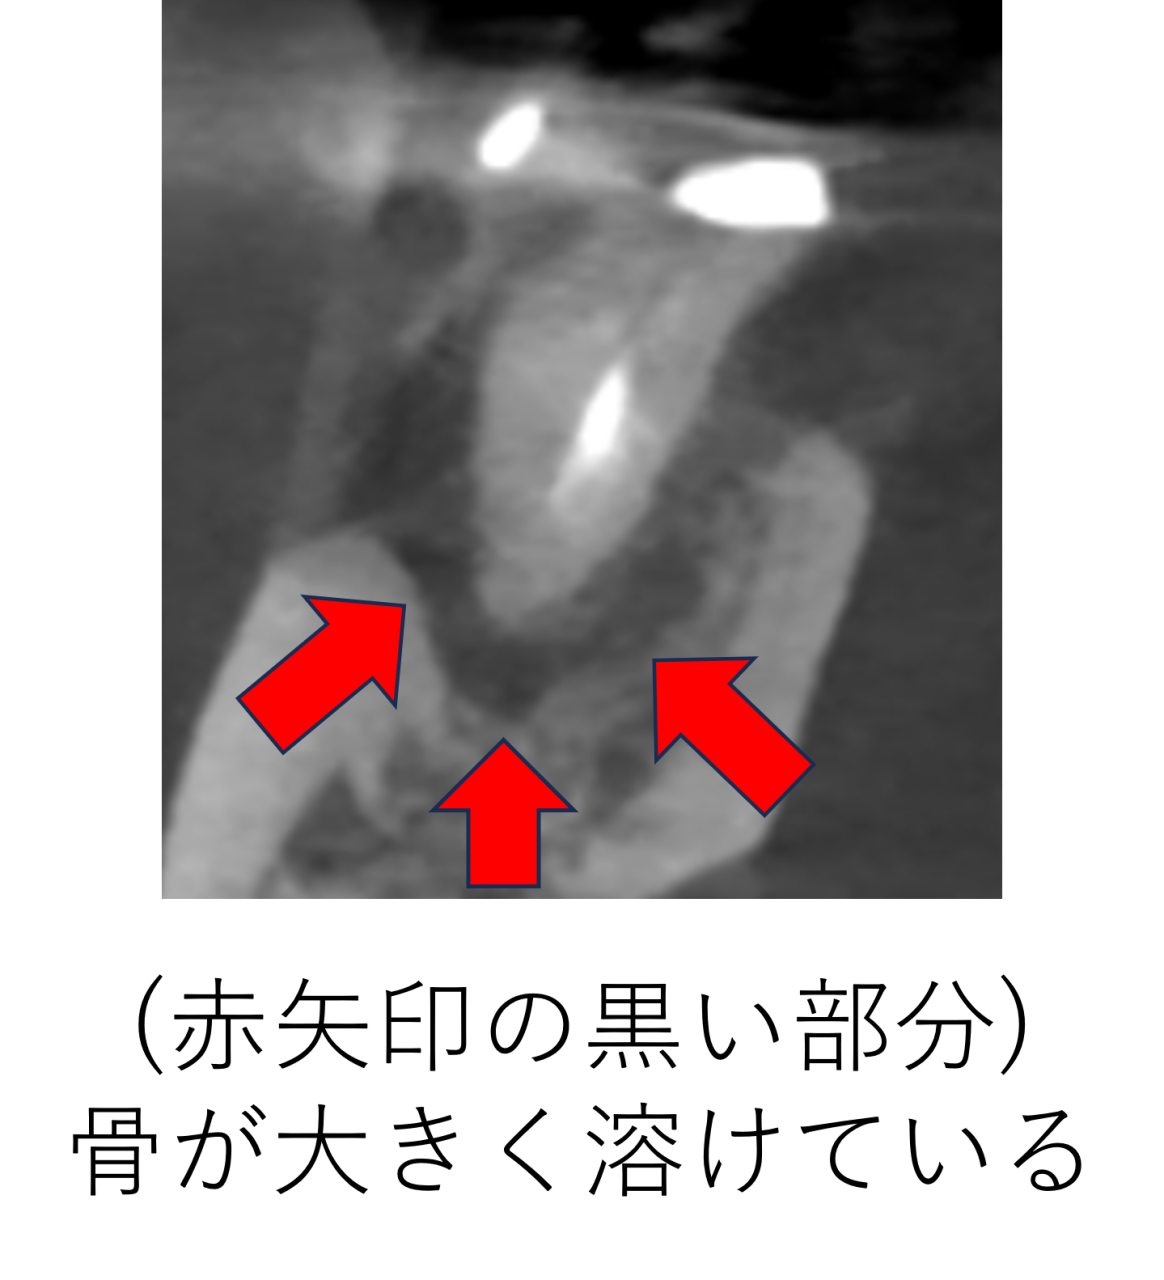

レントゲンを詳しく確認しました。横からの断面図を見ていくと、以前の治療で神経を取って薬をつめているのですが、神経の取り残しがあり、薬が根の先まで十分に入っていません。取り残された神経が腐ってしまい、根の中で細菌が繁殖し、根の外に出てしまい顎の骨を溶かしてしまっています。

前からの断面図を見ると、黒い部分が骨が溶けているところですが、とても広範囲にわたり骨が溶けているのがわかります。

上からの断面図を見ると、この歯はUの字の形をしています。この場合神経の形がとても複雑になるので、治療は難しくなります。

この形の場合、このUの真ん中のところにも神経があることがほとんどなので、おそらく神経の大元の部分も取り残されている事が予想されました。

立体化した画像では、骨が溶けてしまい大きな穴が開いてしまっています。歯の根っこが丸見えの状態です。